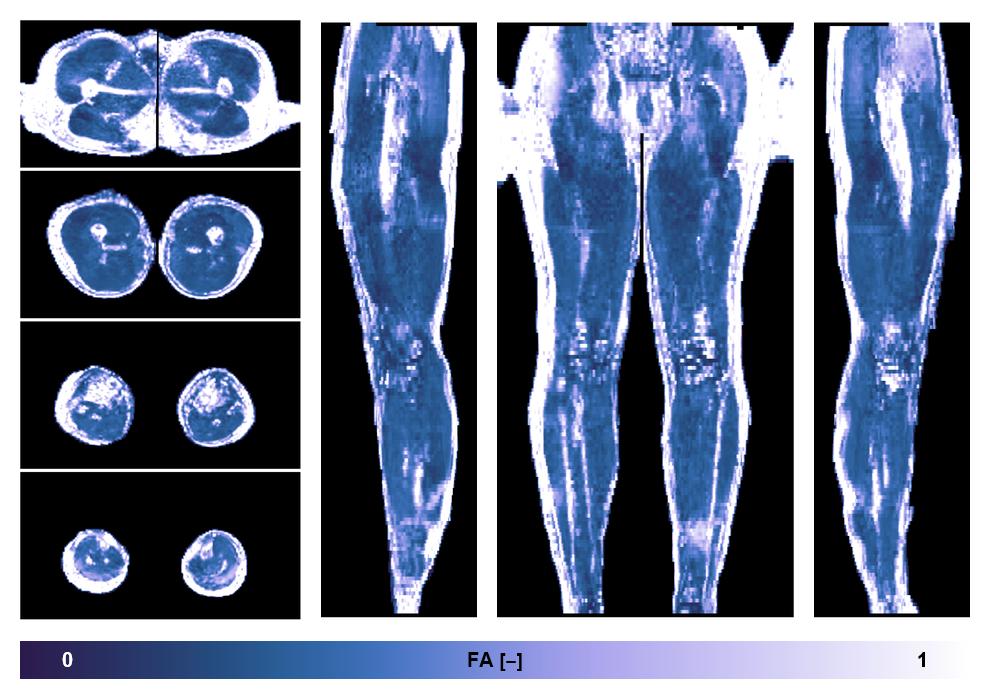

• Fractional anisotropy

IVIM corrected whole leg muscle fractional anisotropy obtained from diffusion tensor imaging.